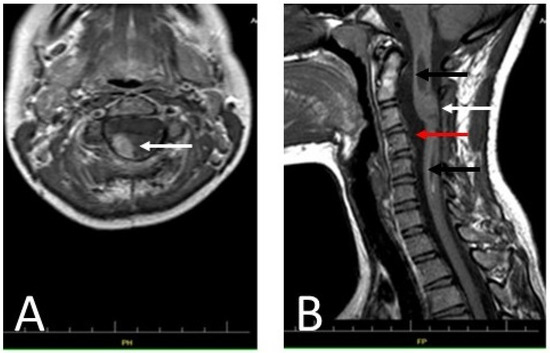

2. Case Presentation